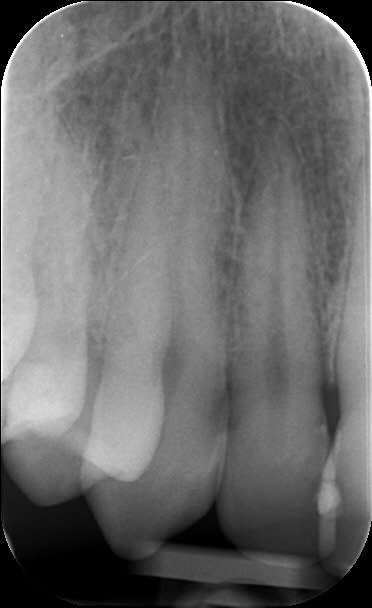

J'ai acheté le Aenial et essayé aujourd'hui sur 3 compos : 11D, 21M, 22M.

Quelques problèmes restent encore pour trouver la teinte de base avec leur teintier. J'ai pris un Vita.

J'ai passé du temps même si j'ai pris plus que les SC.

Retour d'expérience avec du Gaenial après quelques cas. Ca tient bien la route, cependant il faut oublier le pinceau silicone qui étale mal ce produit. C'est moins évident de caractériser les bords libres, on obtient une sorte de flou de translucidité entre le transparent TE (opalescent?) et les teintes émail (le plus souvent JE), ce n'est pas aussi net et délimité que chez Micérium, mais l'effet caméléon est cependant plus présent avec le GC ce qui permet d'obtenir un bon résultat plus rapidement. Pour le cas présenté ça donne environ 1H30 pour 2 composites "spot" sur 13 (mésial) et 12 (disto-palatin), 1 composite de bonne taille sur 12 (mésio-vestibulaire), et 2 facettes composite directes sur 11 (vitale), et 22 (dévitalisée), y compris pose/dépose digue, retouche bord libre de la CCM (antédiluvienne), mise en forme et polissage à 90%

Puis 15 minutes de polissage/brillantage 1 semaine après.

Le résultat n'est pas aussi naturel qu'avec le Micérium, mais on est dans du bon niveau tout de même et je pense avoir économisé une bonne heure, avec un peu plus d'expérience et en se défaisant de certains "tics" lié à l'habitude du Enamel HFO, on devrait encore gagner un peu de temps......ça va faire plaisir à la cnsd et à la sécu ça!!!!